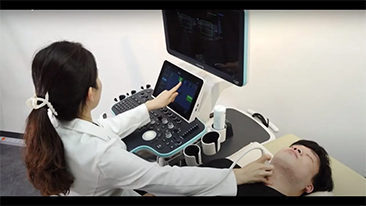

Resona 7

Nuove tendenze nellŌĆÖinnovazione dellŌĆÖecografia

Fin dalla sua fondazione Mindray esplora continuamente nuovi modi per migliorare l'affidabilit├Ā diagnostica. Equipaggiata con la pi├╣ rivoluzionaria tecnologia ZONE Sonography?, la nuova piattaforma ZST+ di Resona 7 porta la qualit├Ā dell'immagine ecografica ad un livello superiore con l'acquisizione per zone e l'elaborazione dei dati canale.

Oltre alla qualit├Ā delle immagini di livello eccellente, Resona 7 migliora anche le capacit├Ā di ricerca clinica il rivoluzionario V Flow per la valutazione emodinamica vascolare, e l'acquisizione piani pi├╣ intelligente dal set di dati 3D per la diagnosi del sistema nervoso centrale fetale. Combinando il pi├╣ intuitivo funzionamento multi-touch basato su gesti e tutte le caratteristiche cliniche essenziali, Resona 7 sta veramente portando nuove tendenze nellŌĆÖinnovazione dellŌĆÖecografia.